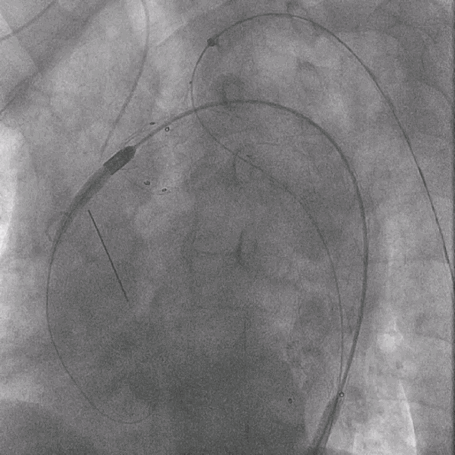

植入华脉泰科覆膜支架

泥鳅导丝怎么用曲乐丰教授团队:0.018"和0.035"普通泥鳅导丝行胸主动脉弓上分支原位开窗的病例分享_https://www.jmylbn.com_新闻资讯_第29张

释放华脉泰科支架前三节,再次造影确认位置

泥鳅导丝怎么用曲乐丰教授团队:0.018"和0.035"普通泥鳅导丝行胸主动脉弓上分支原位开窗的病例分享_https://www.jmylbn.com_新闻资讯_第30张

全部释放并造影确认支架形态